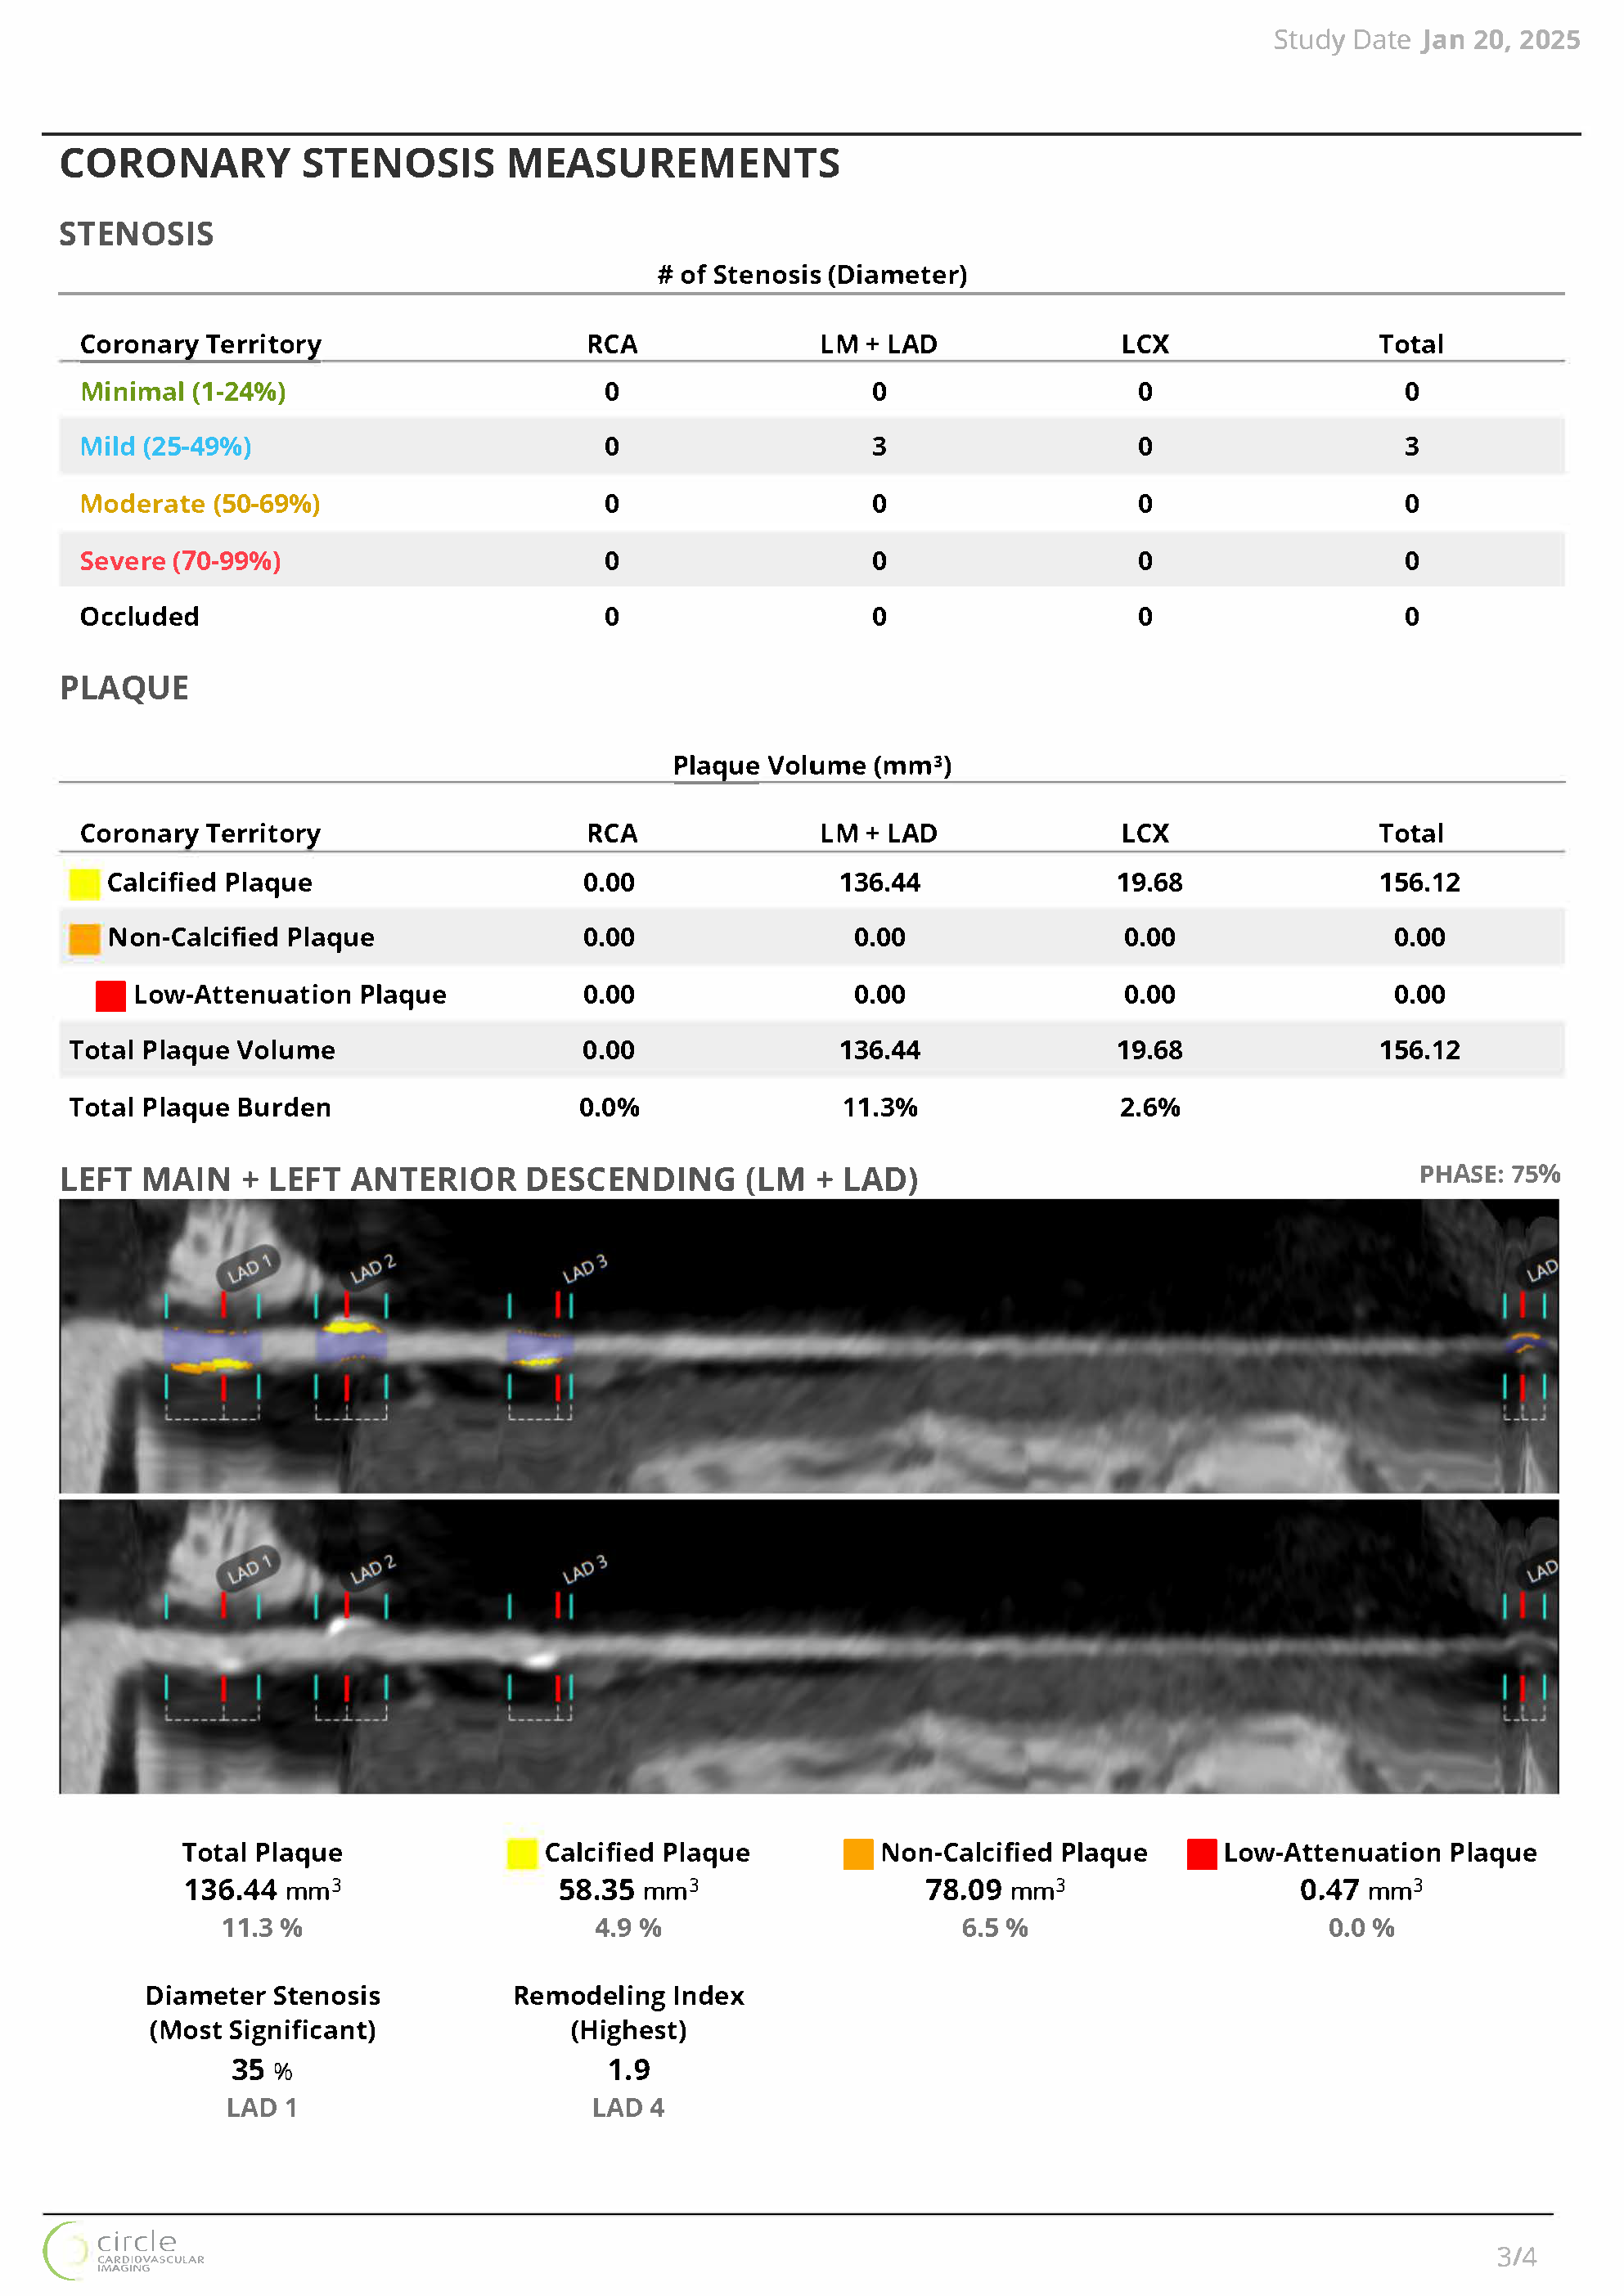

Smart, Actionable Reporting

- Generate vessel-level and total plaque summaries for fast and

clear interpretation - Visual, patient-friendly outputs improve communication and support shared decision-making

- Integrated CAD-RADS classification supports standardized reporting and facilitates communication across the care team